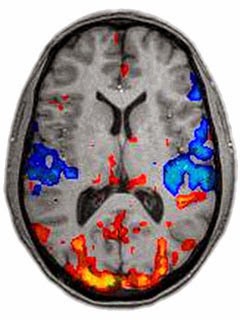

Los sistemas actuales de escaneado por resonancia magnética DTI recogen ya el movimiento de fluidos en las fibras nerviosas. Existen otros métodos de captura como la resonancia funcional, que da pistas de la actividad general de las neuronas en un área, pero ninguno de estos métodos ofrece el detalle requerido para ver las conexiones individuales y sus propiedades dinámicas.

Por otra parte, estos sistemas de escaneado no destructivo son muy útiles para obtener un conocimiento general del cerebro y su actividad. Se usan para investigar enfermedades como el Alzheimer o el autismo, como puede verse en el maravilloso vídeo que sigue, donde se examinan partes del cerebro de un niño autista de siete años: